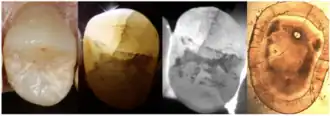

Enamel Fracture

4. Transillumination

Transillumination involves using fiber-optic light to illuminate the tooth surface, with light diffraction at the crack helping to locate it (Chanchala HP et al., 2022).